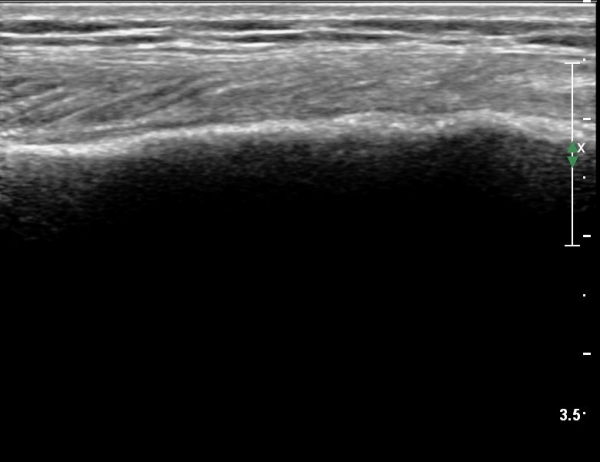

[¹«¸­] °æ°ñ ÇǷΰñÀý ÃÊÀ½ÆÄ¼Ò°ß(sonographic findings of stress fracture of tibia)

±º´ë¿¡ ÀÔ´ëÇÏ¿© ÈÆ·ÃÀ» ¹ÞÀº º´·ÂÀÌ Àִ ȯÀÚ´Â ¾à 2ÁÖ ÀüºÎÅÍ ¹ß¸ñ ºÎÀ§ÀÇ ÅëÁõÀÌ ÀÖ´ø Áß

ÃÖ±Ù¿¡´Â ¹ß¸ñ À§ ¾Æ·§´Ù¸®¿¡ ÅëÁõÀÌ ¹ß»ýÇÏ°í ½ÉÇÏ°Ô °ÉÀ¸¸é ½ÉÇØÁö´Â ¾ç»óÀÓ

ÃÊÀ½ÆÄ °Ë»ç

¹Ì¼¼ÇÏ°Ô ¿¬ºÎÁ¶Á÷ ºÎÁ¾°ú °¡°ñ Çü¼ºÀÌ °üÂûµÊ.